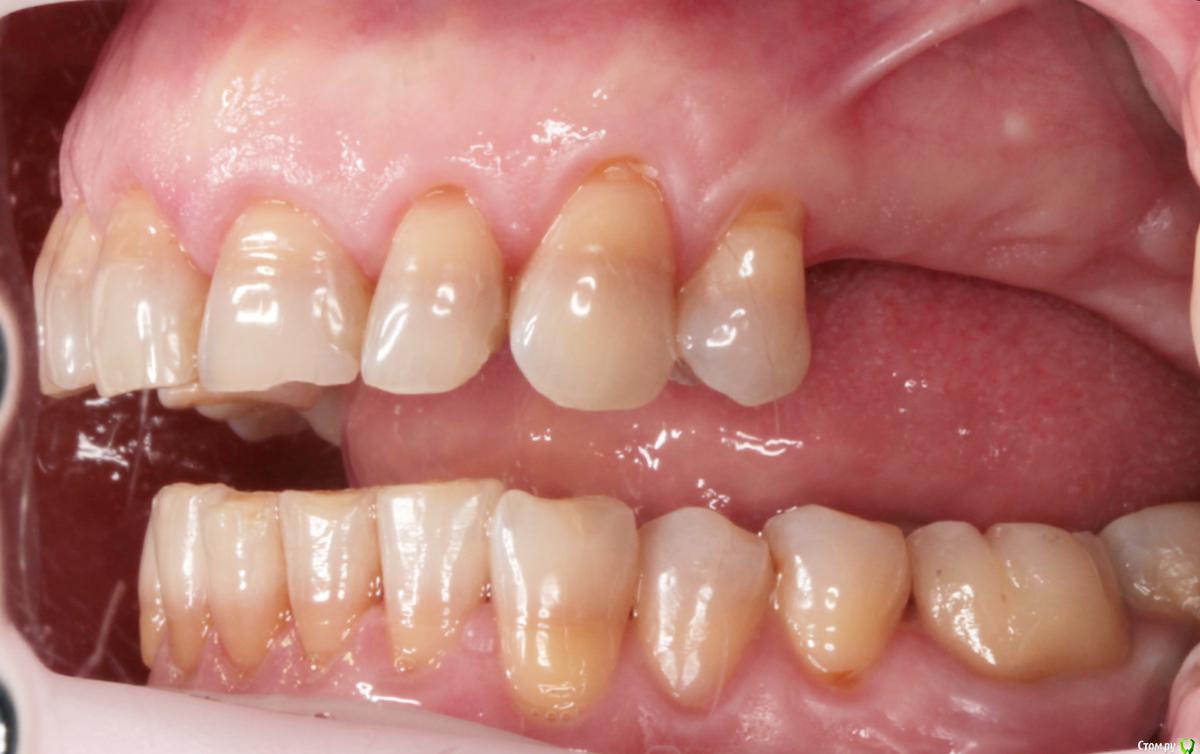

Пациентка пришла с целью восстановления отсутствующих 15,16,17,24,27 з.

Из анамнеза - хронический двухсторонний синусит, соответствующие зубы удалены более 5-ти лет назад, тетрациклиновые зубы ( от изменения цвета отказалась ).